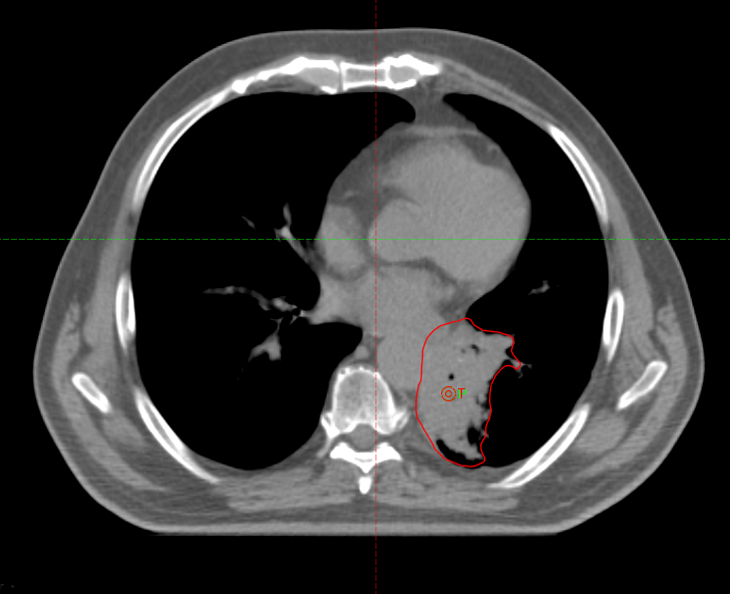

Пациент пришел с жалобами на выраженную одышку, кровохарканье

Во время СВСТ при первом сеансе ЛТ выявлен ателектаз левого легкого

22.07.2022г. выполнена повторная

КТ- топометрия органов грудной клетки

08.08.2022 на СОД 22 Гр выполнена повторная

КТ- топометрия органов грудной клетки

Курс химиолучевой терапии продолжен по плану